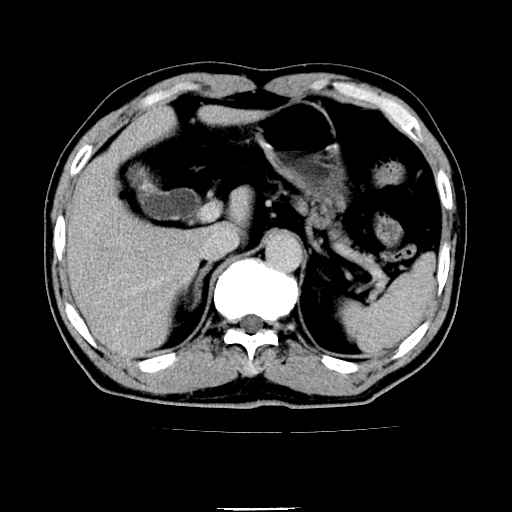

以下是引用chenqiong在2010-3-25 20:56:00的发言:[br]1、胆囊炎,胆囊息肉[br]2、肝内胆管及胆总管扩张,胆总管下端结石[br]3、十二指肠乳头旁憩室

以下是引用zxl51642在2010-3-26 10:47:00的发言:[br]胆囊炎,胆囊息肉,胆总管扩张,但未看到明显肿块,肝内胆管扩张不像恶性,炎性狭窄或阴性结石可能吧,建议mrcp,右肾小囊肿